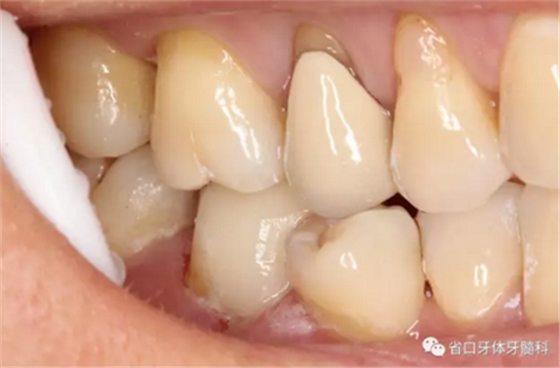

圖15-17 術后1年5個月回訪:患者使用良好,無明顯食物嵌塞,牙周健康,瘺管未見復發(fā)。